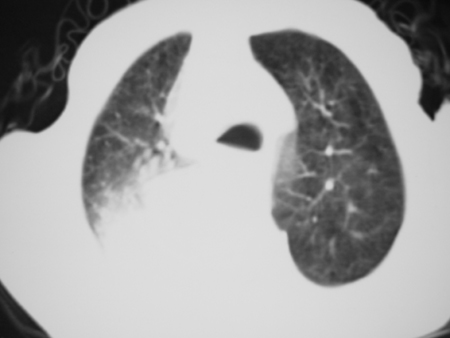

男77岁,胸痛就诊

右侧胸腔积液,部分包裹,右下肺膨胀不全,右下肺感染。

右侧胸腔积液,部分包裹,右下肺膨胀不全,右下肺感染